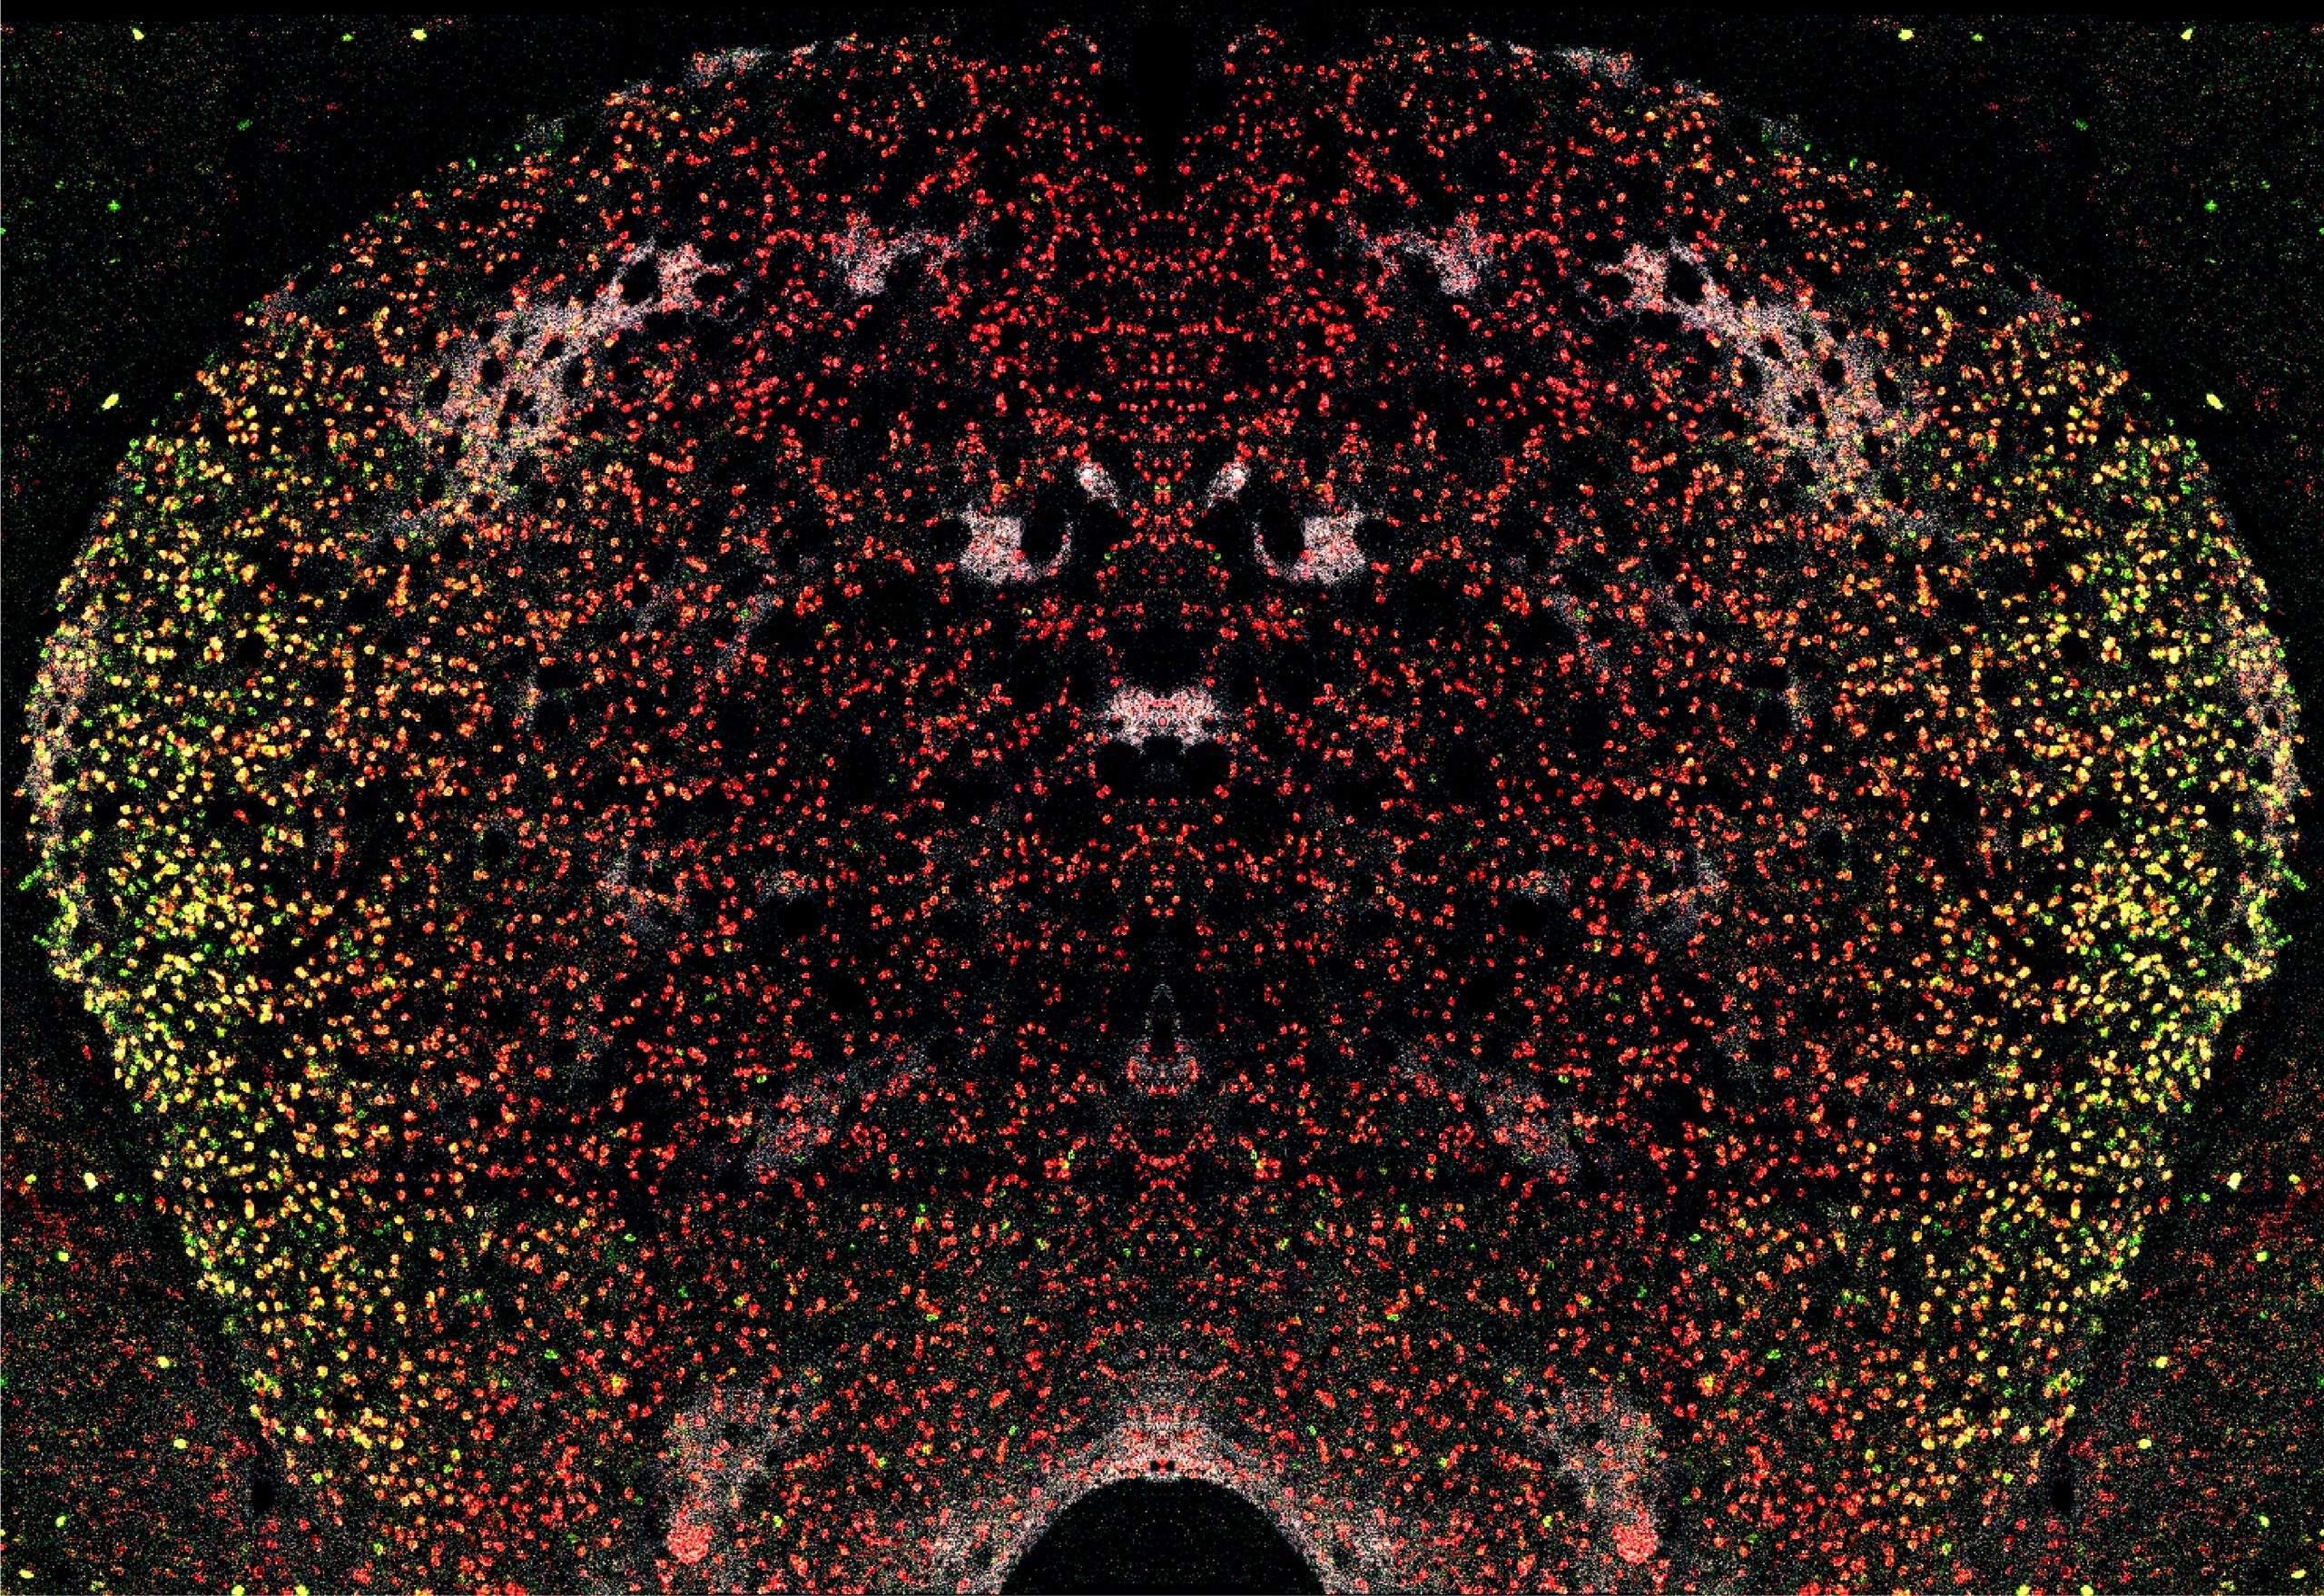

Sur cette photo, on peut observer une image symétrique et réfléchie du striatum, imagé obtenu à l’aide de la microscopie confocale à fluorescence. Les récepteurs CB1R sont en rouge et les récepteurs dopaminergiques de type 2 en vert. En blanc sont représentés les récepteurs µ-opioïdes.